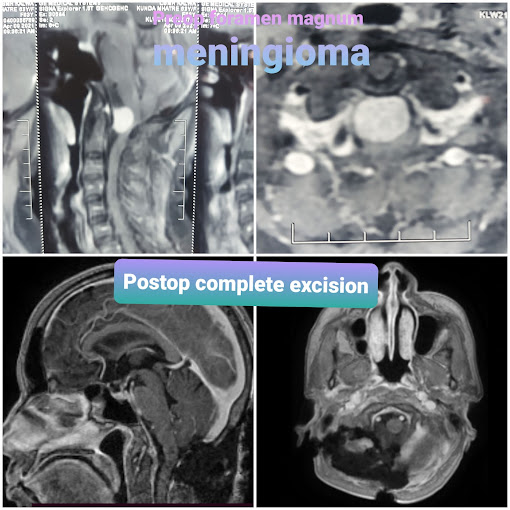

Dr Bharat Shinde completed his M.Ch Neurosurgery from the National Institute Of Mental Health And Neurosciences (NIMHANS), Bangalore which is an institute of National importance.